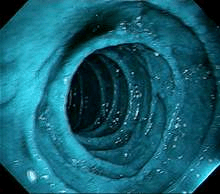

mBLU uses multi-LEDs of wavelength between 400-700nm & 450nm for enhanced mucosal and submucosal tissue visualisation. The brighter and clearer images provided by the mBLU technology enable Image-Enhanced-Endoscopy (IEE) and help detect and characterize lesions/polyps better, thus improving the chances of detecting early-stage cancer and providing high-quality lifecare.

mBLU1 enhances mucosal tissue structure visualisation, improving diagnostic yield and lesion characterization. Its spectral imaging helps detect early-stage esophageal cancer, Barrett’s dysplasia, and minimal esophagitis.

mBLU2 leverages Blue Light technology to enhance submucosal vascular microarchitecture visibility, improving early cancer detection. mBLU 2 is optimised to offer a close-up or detailed view to penetrate the superficial epithelium and differentiate adenoma from invasive cancer.